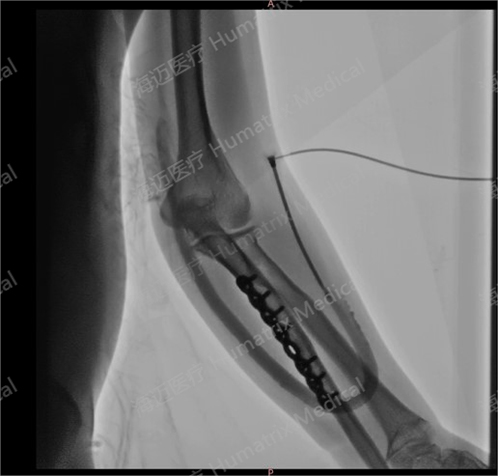

臨床試驗患者使用LineMatrix耐邁通?生物型人工血管長期血液透析,血管造影通暢。